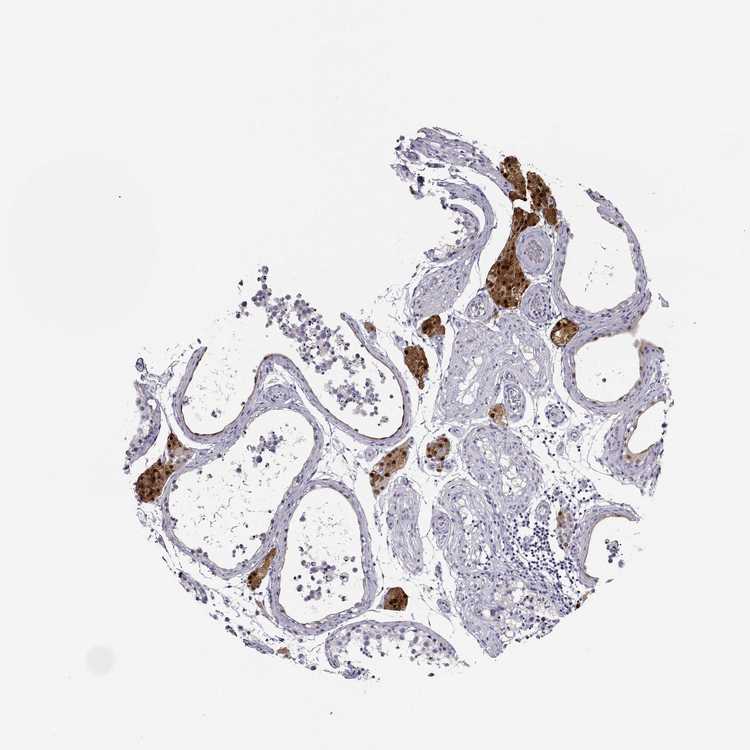

TESTIS - Antibody stainingi

Antibody staining in the annotated cell types in the current human tissue is reported as not detected, low, medium, or high, based on conventional immunohistochemistry profiling in selected tissues. This score is based on the combination of the staining intensity and fraction of stained cells.

Each image is clickable and will lead to virtual microscopy that enables deeper exploration of all samples and also displays staining intensity scores, fraction scores and subcellular localization as well as patient and tissue information for each sample.

Antibody HPA007305Antibody HPA007306Antibody CAB000106

Leydig cells HighHighHigh

Cells in seminiferous ducts Not detectedMedium-